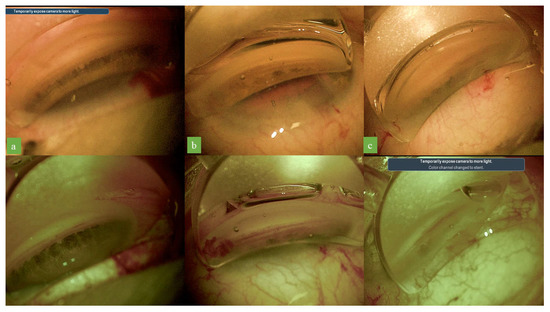

Figure 2.

Standard colors gonioscopic images in three cases (a–c) and corresponding images after optimized digital settings application. Visualization of both the pigmentation of the trabecular meshwork and Schlemm’s canal was enhanced with the optimized digital system.